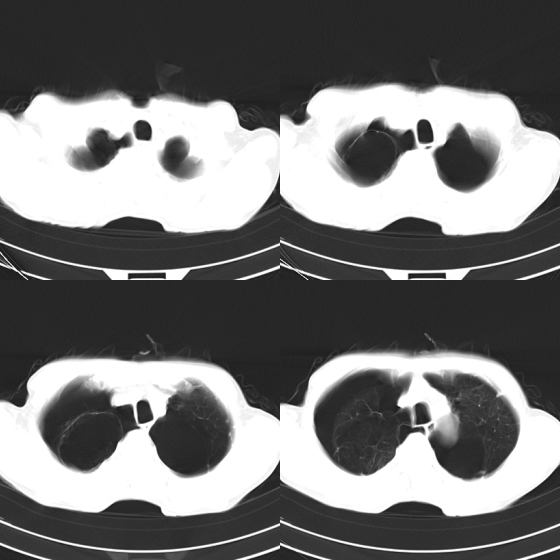

标题: CT21797:M65y,矽肺团块内空洞?

m65y,咳嗽、咯痰,煤工工作史10+年。低热,无明显脓臭痰。临床怀疑tb。

矽肺伴结核 右侧气胸,左肺上叶肺大泡

煤工尘肺,多发肺大泡,右侧气胸.

双侧矽肺,肺大泡,肺气肿

结合临床考虑尘肺并空洞形成,双肺多发肺大泡,右侧气胸。

矽肺伴结核(左肺上叶病灶内空洞形成),右侧气胸,两肺多发性肺大泡。